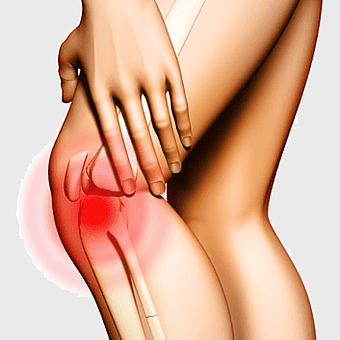

person holding painful knee, knee therapy management, patellofemoral pain syndrome, physical therapy for knee, chronic joint pain relief, lower limb injury treatment, human body musculoskeletal health -

knee pain sports injury, physical therapy for athletes, human knee bones anatomy, joint focus in running, skeletal health in sports, musculoskeletal injury prevention, running biomechanics analysis -

knee pain illustration, joint replacement surgery, arthritis relief, pain management techniques, human anatomy focus, muscle strain remedies, bone health solutions -